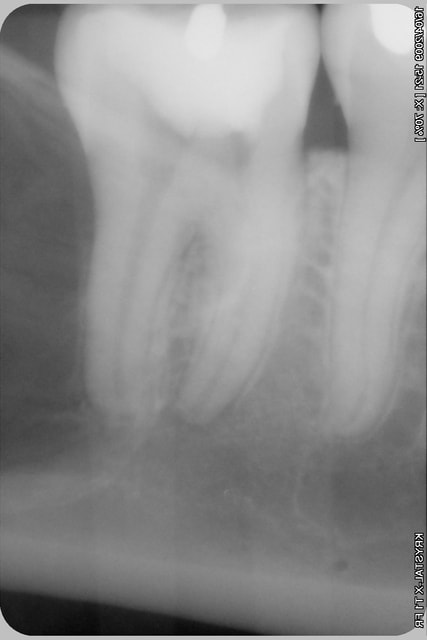

j'attends le resultat de l'irm

et ensuite ....

l'os est fin quand même, non?